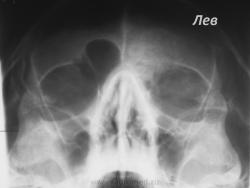

Складывается впечатление, что правая лобная пазуха представлена избыточно развитой ячейкой решетчатой кости - псевдолобная пазуха, левая пазуха отсутствует, возможно, изначально. Верхнечелюстные пазухи не настораживают. Сделать обзорную краниографию в прямой и левой боковой проекции, а далее - томограммы. Думаю, так.

О синуите речь не идет, а вот что касается левой лобной пазухи - прицельный снимок в левой боковой проекции, цель - дифференциация между аномалией (аплазия) и остеомой смешаного характера; если сомнения останутся - КТ.

на обычный синусит неочень похоже, контуры стенок пазухи не дифференцируются вообще, еще и верхняя часть глазницы пострадала. Пока мысли об онко...мукоцеле... Дообследование обязательно, ЛОР сам определит алгоритм действия.

Мукоцелле в лобной слева?

Остеохондрома верхнемедиальной стенки левой орбиты.